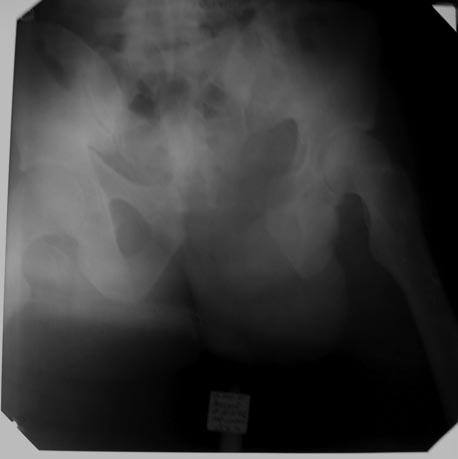

Почему-то только один снимок загружается (послеоперационный). Есть проекции inlet-outlet, КТ?

Снимок от 05/03/2013 см. выше.

Я бы обратил бы внимание на состояние правого тазобедреннего сустава. Возможно из-за проекции, но проксимальное бедро во внутренней ротации, укорочение и неправильная Шентон линия. Отдельный снимок тазобедреннего сустава или КТ.

Вы обратили внимание на межвертельный перелом или перелом шейки правой бедренной кости правой бедренной кости, кажется там еще есть укорочение, и смещ. отломков. Я бы обратил на это внимание. Может быть я ощибаюсь . Возможно у Вас есть КТ.

Извините Юрий, не очень хорошо видно, а проксимальный отдел правого бедра и седалищная кость слева - не сломаны?

Но у вас мне кажется ещё одна проблема. Посмотрите правый

проксимальный отдел бедра. Ощущение, что есть перелом шейки, который из вколоченного превратился в расколоченный(сделайте укладку по

Лауэштейну и всё увидите).

Это типичное осложнение, причиной которого является пренебрежение фиксации разорванного илеосакрального сочленения. Андрей Середа прав, что-то там с проксимальным отделом правого бедра не все благополучно, похоже есть базальный перелом. Наверно поэтому больной и правую ногу не нагружал? Нагружал левую половину таза с нефиксированным задним повреждением тазового кольца. Осложнение закономерно. Что делать? Реостеосинтез: спереди симфиз пластиной (или опять двумя), сзади илеосакральные винты слева (или с обеих сторон? СТ делали?). И с проксимальным отделом правого бедра разбираться...

Юрий Алексеевич приветствую. Отталкиваясь от снимков от 05.03 могу предположить что имеется не только вырывание винтов с лонной кости справа , но и ятрогенный перелом лонной кости нисходящей и горизонтальной ветви справа . Для уточнения конечно КТ обязательно, может быть функциональные снимки на спине и на боку. Если мое предположение имеет место быть то ресинтез имеющимися пластинами практически невозможен. На сколько расхождение симфиза фиксированое(ригидное) ? Какой диастаз на самом деле имеется на сегодняшний день? Если диастаз большой и деформация фиксированная то одноэтапно устранить думаю будет трудновато, Железяки убирать надо в любом случае, далее аппарат - передняя рама , постепенно устранить расхождение, после устранения - винты сзади в КПС(2 шт) и можно вести в аппарате до сращения или пластину но как говорится от "уха до уха". Как выглядит пациент ? На сколько выражен жировой слой , масса пациента? Эти данные очень важны для принятия решения... И конечно с шейкой бедра тоже надо разобраться

Уважаемые коллеги! Спасибо Артуру Аслановичу и Александру Николаевичу за поздравления! Впечатляет масса различных мнений и советов, особенно ненавязчивые сомнения по поводу "проблемы" правого тазобедренного сустава. Мне тоже "кажется", однако эта проблема, безусловно, называется базальный перелом шейки правого бедра, что подтверждается измененным шеечно-диафизарным углом почти до прямого, нарушением линии Шентона и дуги Адамса. Учитывая время, прошедшее с момента травмы, молодой возраст пациента, нельзя исключить, что уже имеются признаки коснолидации, тогда, увы, будет необходима открытая репозиция с коррекцией смещений и фиксация (согласна с А.А.Волной) DHS.